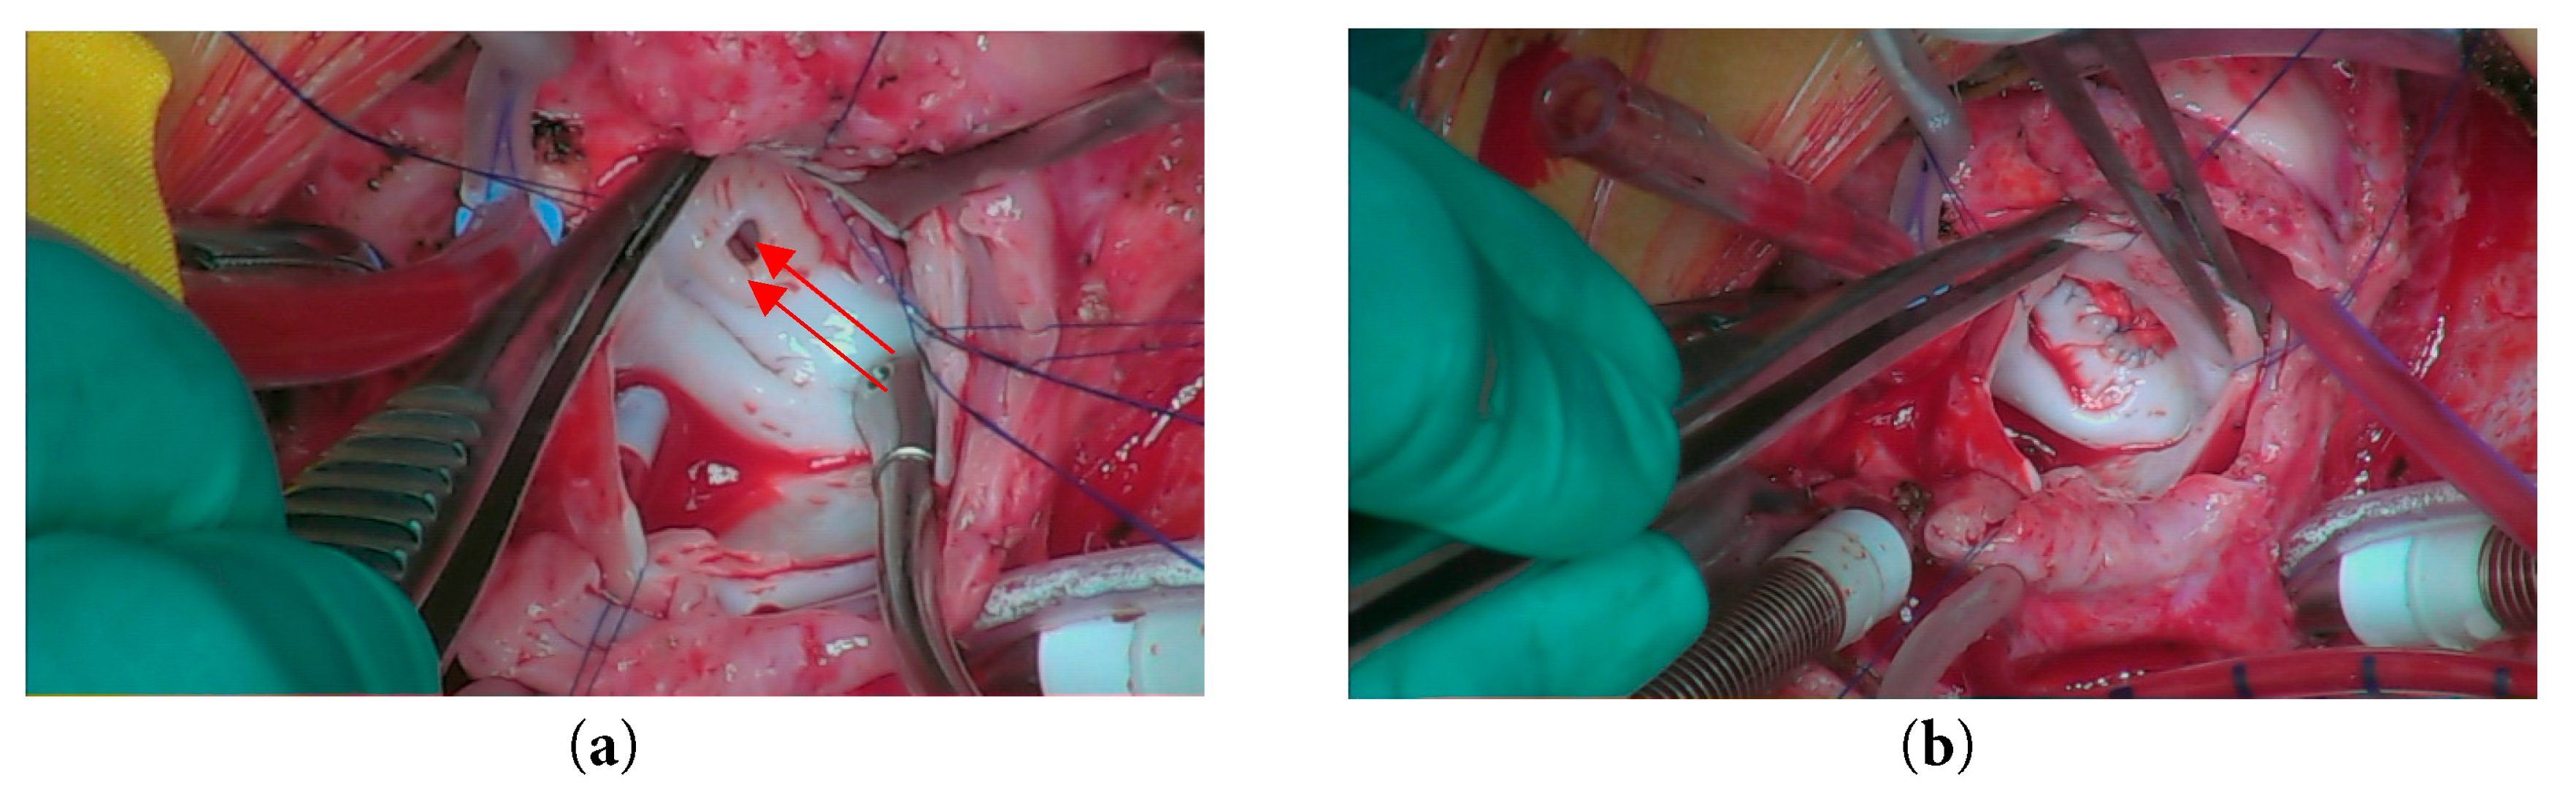

She then underwent an emergency surgery of redo median sternotomy and closure of aneurysm. The right atrium was opened, and a trans-septal approach was made to access the left atrium and mitral valve. Intraoperative inspection revealed that the mitral valve was structurally intact, and the previously noted vegetation had resolved. An atrial aneurysm was identified. A pericardial patch was fashioned and secured to the entry hole using pledgeted 6-0 Cardionyl sutures in an interrupted manner (Fig. 5). The exit hole was closed with a continuous suture technique. The atrial septum was subsequently repaired, and the right atrium was closed using 6-0 Prolene sutures. The chest was closed in the standard fashion, utilizing six stainless steel sternal wires, with mediastinal and pleural drains in situ. The skin and subcutaneous tissue were approximated and closed routinely. The patient was transferred intubated to the cardiac intensive care unit (CICU) with stable hemodynamics for further monitoring and care.

Figure 5: Intraoperative view showing (a) Opening of the left atrial aneurysm; (b) Closure of the aneurysm using a pericardial patch.